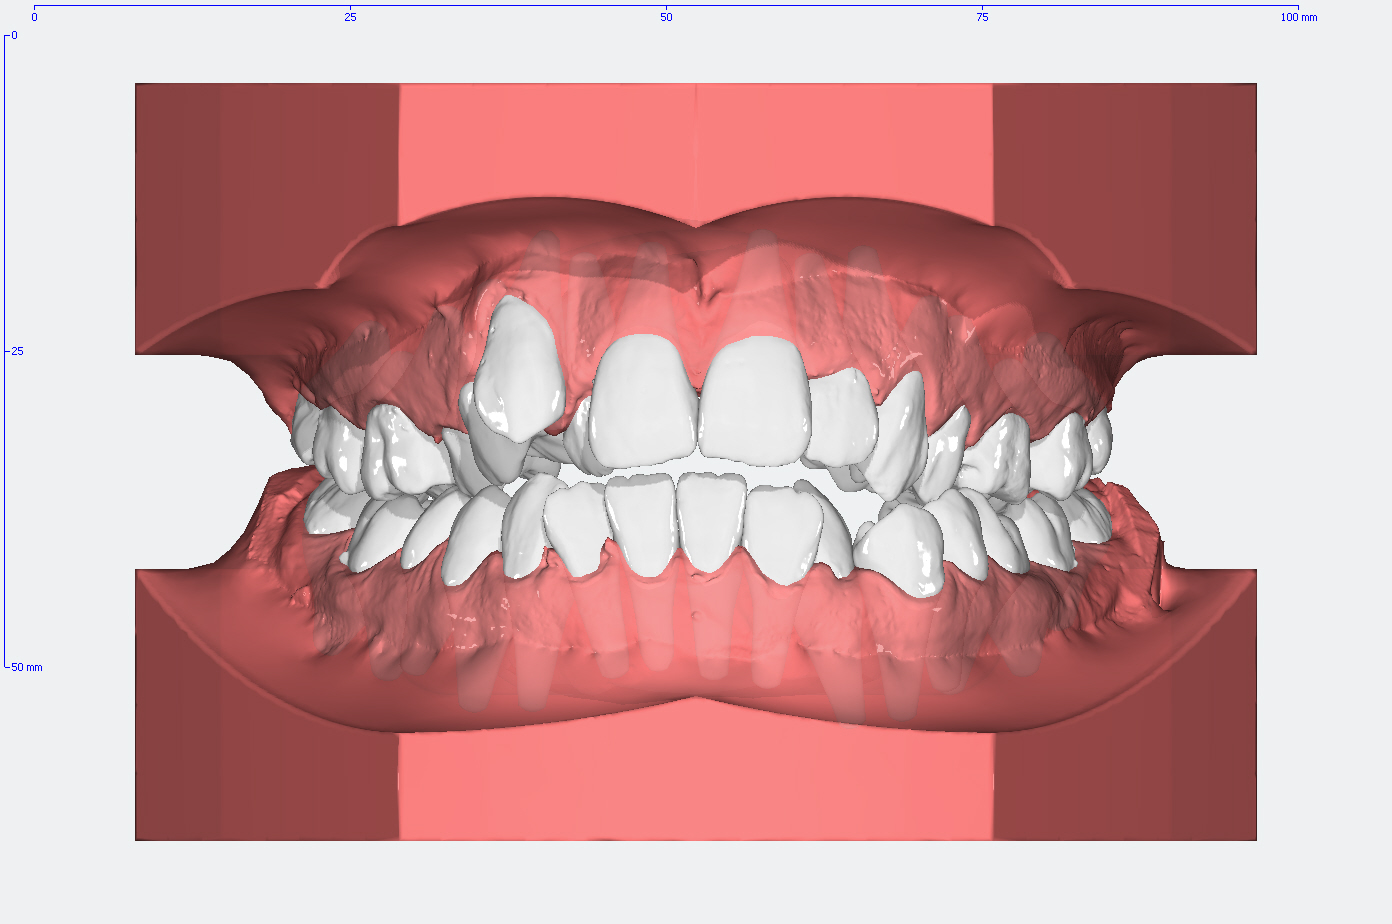

Die Entwicklung der Zahnstellung im Gebiß anhand von 3D Modellen

In den Abbildungen unten sehen Sie den Vergleich der Zahnstellung in den Gebissmodellen in der ursprünglichen Form und nach der kieferorthopädischen Behandlung.